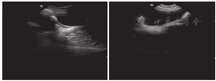

血尿便常规、血生化、甲状腺功能、脑脊液、胸片、心电图、肝胆胰脾+双肾上腺B超、染色体核型、尿有机酸分析及血氨基酸、肉碱和琥珀酰丙酮检验均无异常。雌二醇、孕酮、睾酮、催乳素、促卵泡生成素、促黄体生成激素均正常;血清极长链脂肪酸(VLCFA)正常。肌电图:多发性周围神经源性损害肌电改变(主要累及感觉、运动神经脱髓鞘)。听觉诱发电位:重度双侧感音神经性听力损失;先证者脑电图:异常儿童脑电图(背景活动减慢);其姐脑电图:正常青少年脑电图;先证者8岁头颅MRI:小脑脑沟宽深。其姐14岁头颅MRI:双侧小脑半球萎缩(图1)。先证者左腕关节正位片(骨龄片)正常。其姐14岁骨龄片:8枚腕骨发育,相当于10~11岁(图2)。先证者双肾B超正常;其姐双肾B超:双肾形态略小(左肾88 mm×39 mm,右肾85 mm×36 mm)。其姐14岁子宫附件B超:子宫形态小,宫体长经20 mm,前后径7 mm,横经10 mm,双侧卵巢显示不清(图3)。

DBPD是一种罕见的过氧化物酶体单个酶缺陷遗传病[2]。1989年由Watkins等[15]首次描述;1997年明确HSD17B4为其致病基因[16] 。本病以新生儿脑病、多发性神经病、精神运动发育障碍、双侧感音神经性听力损失、肝大、多发畸形为临床特征。目前还发现其他的临床表型,如卵巢功能障碍、小脑功能障碍、运动退化、骨成熟延迟、骨骼畸形等[1,3,4,6,7,8,9,11,17]。本组2例患儿为同胞姐弟,相同表型为新生儿癫痫发作、肌无力、精神运动发育迟缓、共济失调、足部畸形;姐姐还合并卵巢功能障碍、骨骼发育异常。临床电生理表现为双侧感音神经性听力损失、多发性周围神经病变。颅脑MRI示小脑萎缩,符合DBPD的诊断。患儿血清VLCFA正常,推测原因为酶活性残留。2例患儿严重程度有差异,推测原因为存在不同的酶活性残留量。